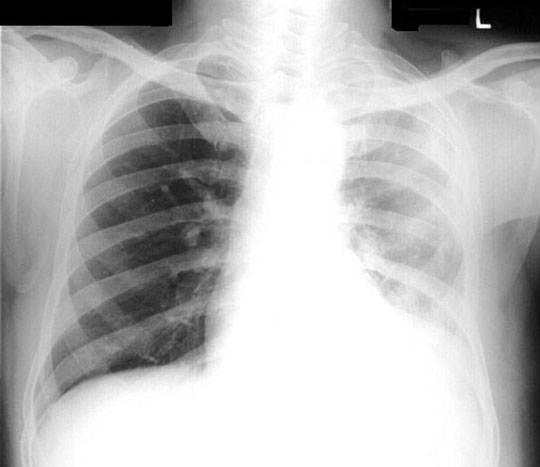

48 year old female presents with low grade fever, dry cough and 12 lbs weight loss in the past two months.

Findings:

• Unilateral haziness

• Smaller left hemithorax

• Chest wall swelling

• Loss of diaphragmatic silhouette

• Blunting of costophrenic angle

• Pleural thickening / Mass

Mesothelioma